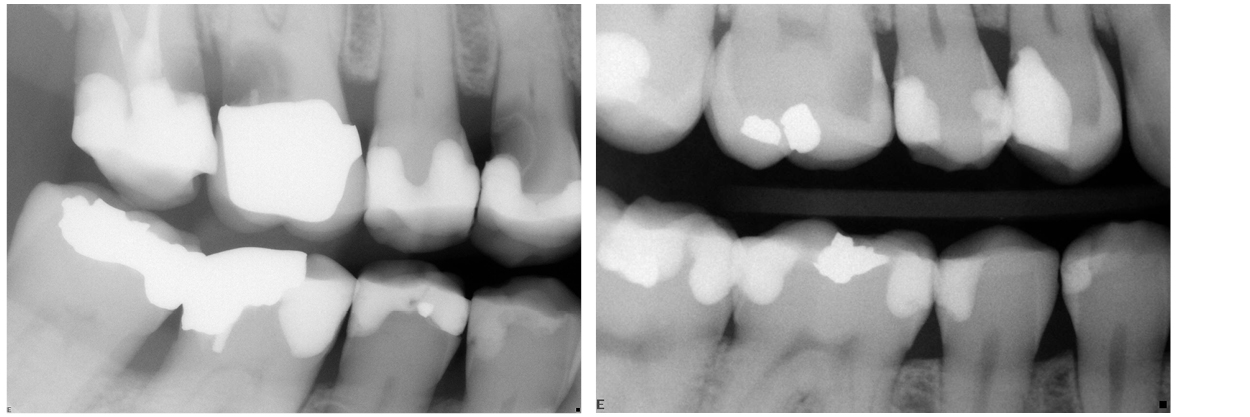

- Hur är kariesangreppets egentliga utbredning i tanden i förhållande till röntgenbilden?